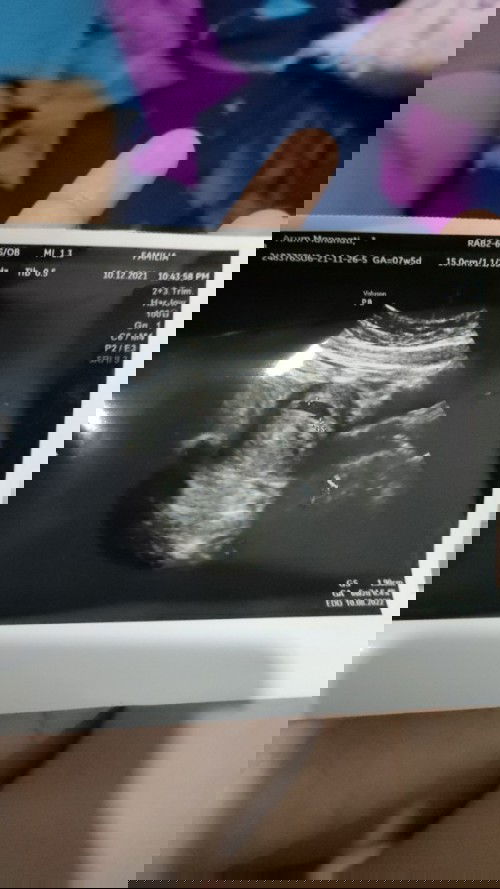

USG 6week2day pada pcos

Assalamualaikum bunda.. Mau sharing USG abdomen 6week2day setelah penantian kurang lebih 8bulan melalu program hamil karena saya PCOS... apakah ada yg sama Bun dengan saya? Doain ya Bun supaya saya bisa merasakan nikmatnya kontraksi, nikmatnya melahirkan, nikmatnya berjuang mengurus bayi 💓